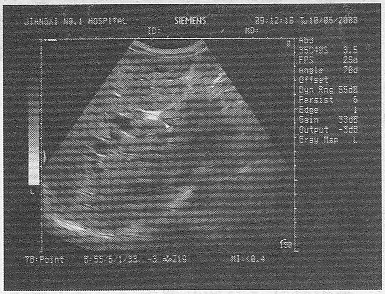

2.男,47岁,上腹部疼痛不适、腹胀,皮肤巩膜黄疸,进行性加重,皮肤瘙痒。声像图如图所示,最可能的诊断为![]() |

| 正确答案:C 解题思路:腹部疼痛不适、腹胀,皮肤巩膜黄染,进行性加重,皮肤瘙痒,声像图显示肝门部结构杂乱,可见一低回声光团,肝内胆管扩张。 |